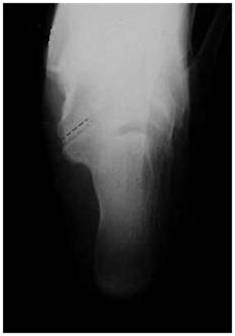

放射学特征:跟距联合在侧位X线片上呈现C sign,跟舟联合在侧位X线片上呈现食蚁兽鼻征 拍摄45°内斜位X片观察跟舟联合。跟骨轴位(Harris and beath): 跟骨轴位X线片观察跟距联合。